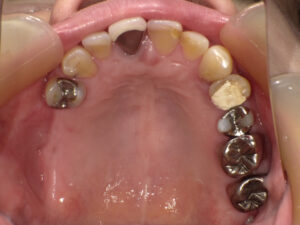

この方は右下がグラグラしているので、噛めるようになりたいという主訴で来院されました。

お口の中の検査・診断をすると残念ながら右下は抜歯という治療方針になりましたが、

歯を抜いた後は、ミラクルデンチャーを入れられました。

術前